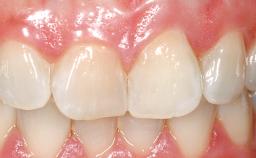

Late Placement of an Implant in a Maxillary Left Central Incisor Site

On examination, the patient had a low lip line and only displayed the coronal half of the anterior teeth when smiling.

Abutment Type Customized

Prosthesis Type FDP